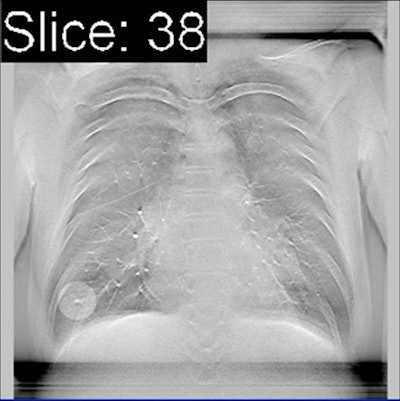

The researchers therefore wanted to see how well CAD would help a group of readers of varying experience levels interpret suspicious lung nodules found on chest tomosynthesis studies. They performed digital tomo and CT exams on a group of 100 patients who were scheduled for exams to evaluate or screen for lung malignancies from December 2012 to June 2013. Fifty of the patients ended up having pulmonary nodules, while 50 did not.

The DR system used was a radiography/fluoroscopy tilt table (Sonialvision Safire, Shimadzu Medical Systems) that was tilted to 80° to reduce motion artifacts as patients leaned back against the table. The system acquired 41 coronal images as the x-ray tube moved around the patient in an arc of 20° over five seconds. The average radiation dose to patients was 0.19 mSv. The CT studies used a standard chest imaging protocol, with an effective dose estimate of 2 mSv to 3 mSv.

The tomosynthesis studies were analyzed with commercially available software (Cadviser TS, Shimadzu) that is optimized to detect lung nodules that are 5 mm to 20 mm in diameter and width (nodules that are smaller and larger than this range are also marked, the authors noted).